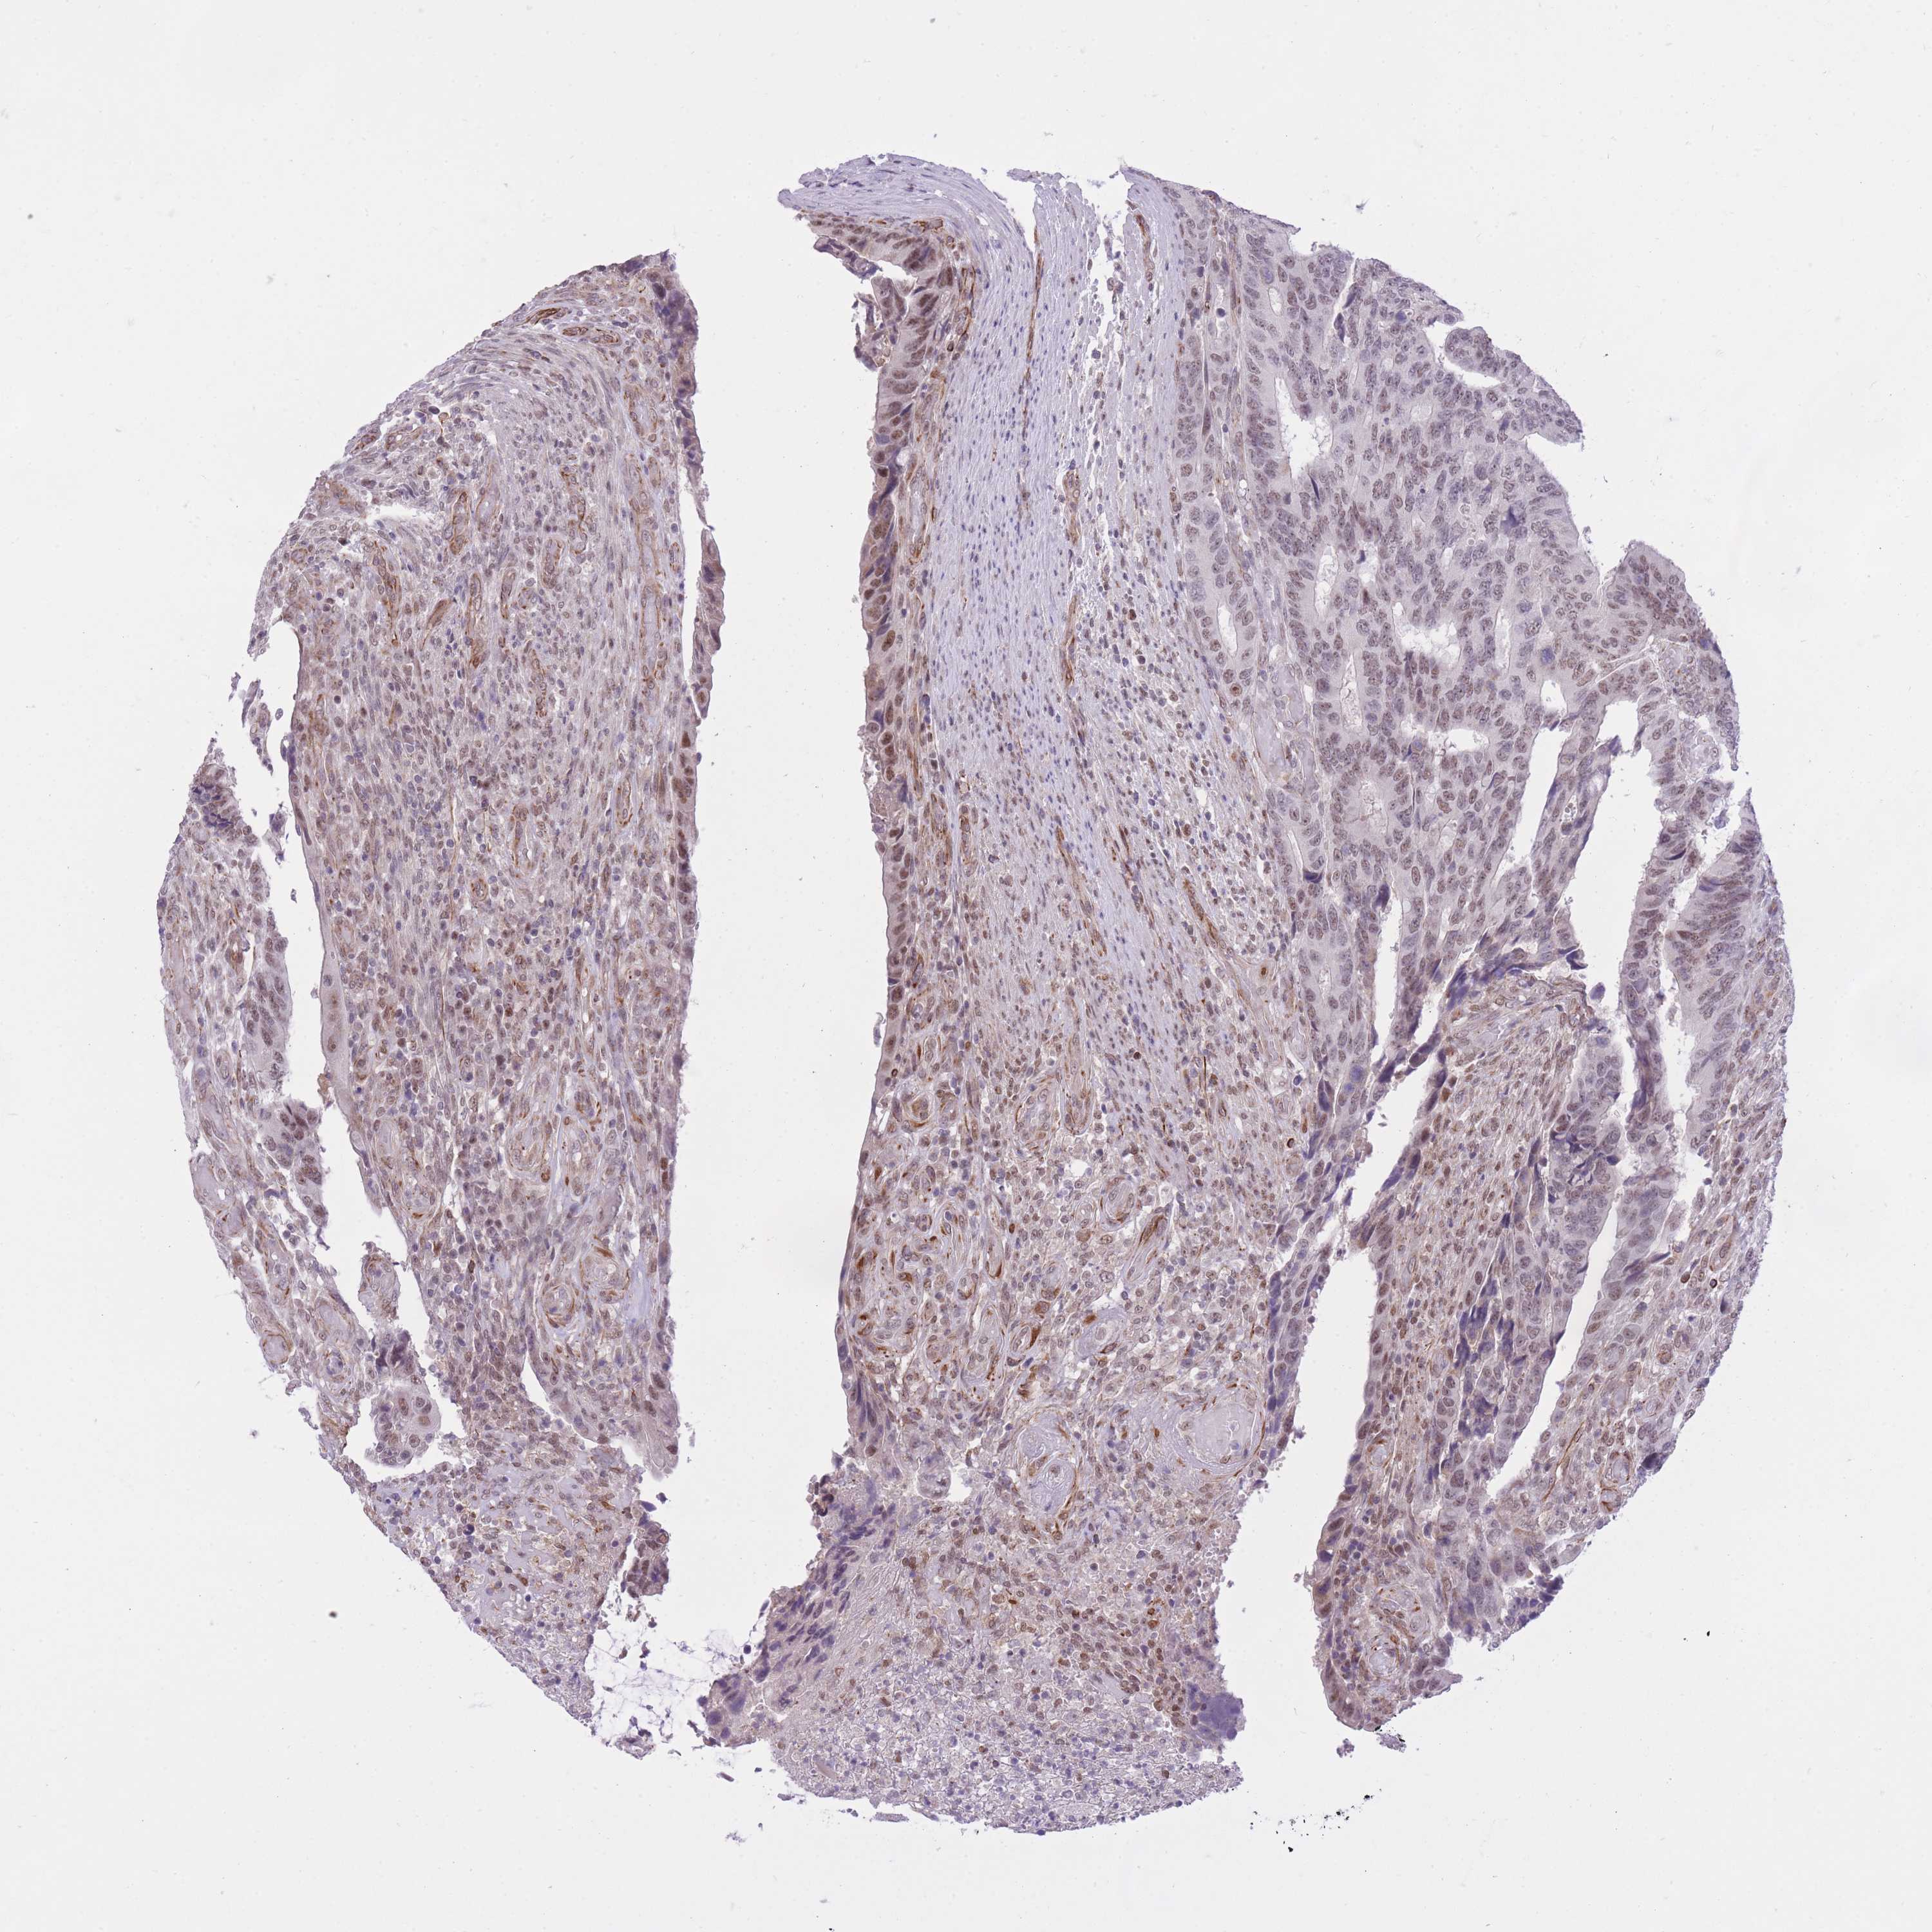

CANCER COLORECTAL CANCER Show tissue menu

COAD TCGA COAD VALIDATION READ TCGA READ VALIDATION PROTEIN COAD CPTAC PROTEIN EXPRESSION

ANTIBODIES

AND

VALIDATION

Colorectal cancer

Human cancer

Colon adenocarcinoma

Rectum adenocarcinoma